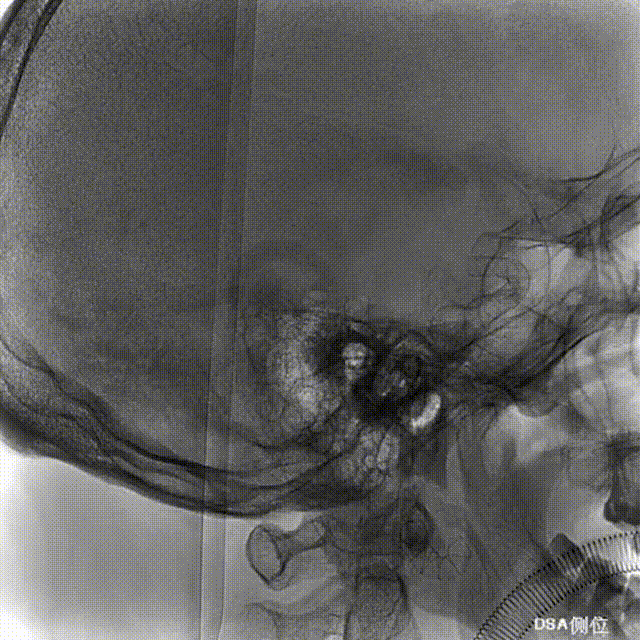

Tubridge Plus Case 1